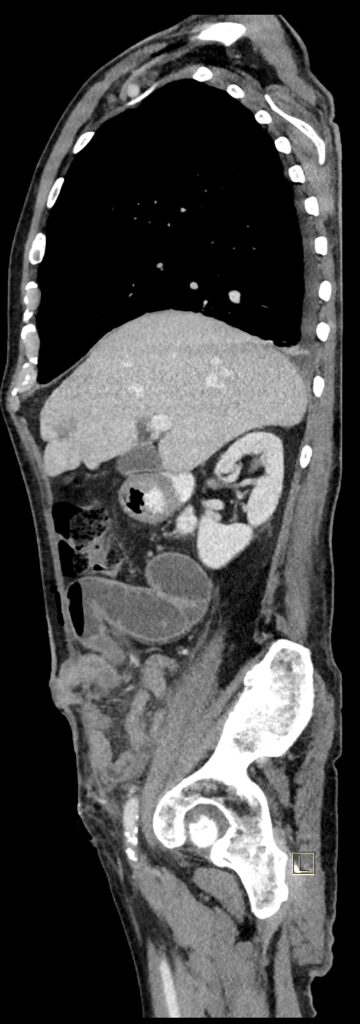

Figura 2: sagital venos din achiziție CT torace, abdomen și pelvis

Discuţie caz nr 124: Pacient postoperator precoce pentru tumoră rectala prezintă simptome de ocluzie intestinală. Examinarea CT evidențiază creștere de calibru a anselor intestinale proximale ce conțin nivele hidro-aerice cu decalibrare la nivelul liniei antero-laterale de partea dreaptă unde evoluează o ansa de intestin subțire. Deasemenea, pacientul prezintă o hernie inghinală stânga fără ca aceasta sa fie cauză de ocluzie, precum și modificări postoperator precoce la nivelul peretelui anterior abdomino-pelvin.